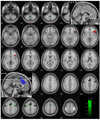

Error detection and behavioral adjustment are core components of cognitive control. Numerous studies have focused on the anterior cingulate cortex (ACC) as a critical locus of this executive function. Our previous work showed greater activation in the dorsal ACC and subcortical structures during error detection, and activation in the ventrolateral prefrontal cortex (VLPFC) during post-error slowing (PES) in a stop signal task (SST). However, the extent of error-related cortical or subcortical activation across subjects was not correlated with VLPFC activity during PES. So then, what causes VLPFC activation during PES? To address this question, we employed Granger causality mapping (GCM) and identified regions that Granger caused VLPFC activation in 54 adults performing the SST during fMRI. These brain regions, including the supplementary motor area (SMA), cerebellum, a pontine region, and medial thalamus, represent potential targets responding to errors in a way that could influence VLPFC activation. In confirmation of this hypothesis, the error-related activity of these regions correlated with VLPFC activation during PES, with the cerebellum showing the strongest association. The finding that cerebellar activation Granger causes prefrontal activity during behavioral adjustment supports a cerebellar function in cognitive control. Furthermore, multivariate GCA described the "flow of information" across these brain regions. Through connectivity with the thalamus and SMA, the cerebellum mediates error and post-error processing in accord with known anatomical projections. Taken together, these new findings highlight the role of the cerebello-thalamo-cortical pathway in an executive function that has heretofore largely been ascribed to the anterior cingulate-prefrontal cortical circuit.